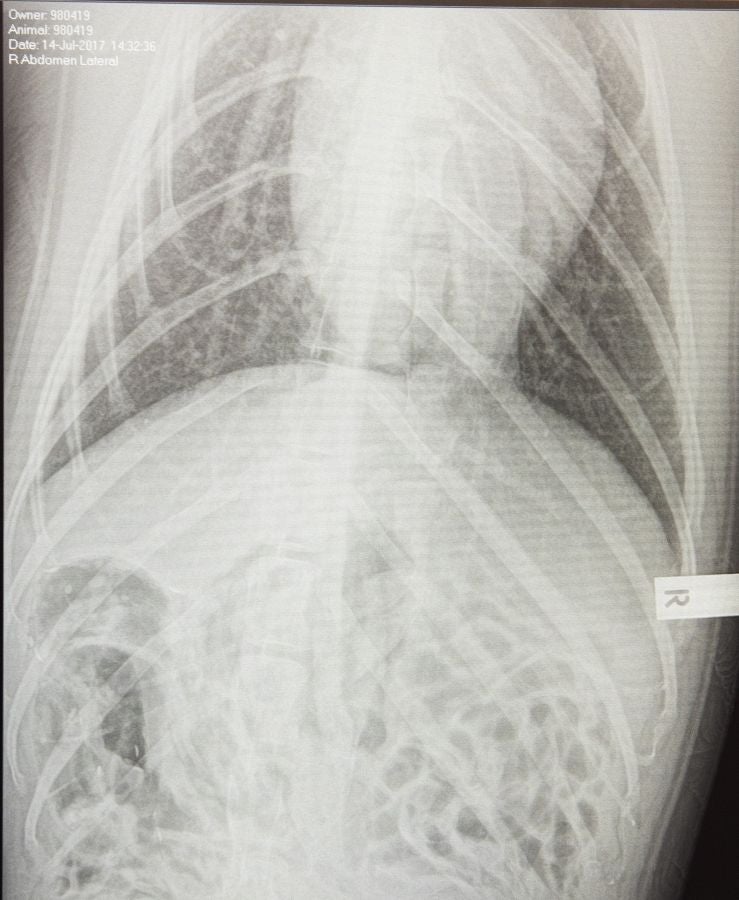

Un veterinario monitoriza la artritis de Tarwin, una foca que se encuentra en el zoológico de Melbourne, Australia. La artritis puede aparecer en gran número de animales envejecidos por eso, el equipo veterinario en el zoológico de Melbourne tiene estrategias para mantener la calidad de vida de los ejemplares afectados.